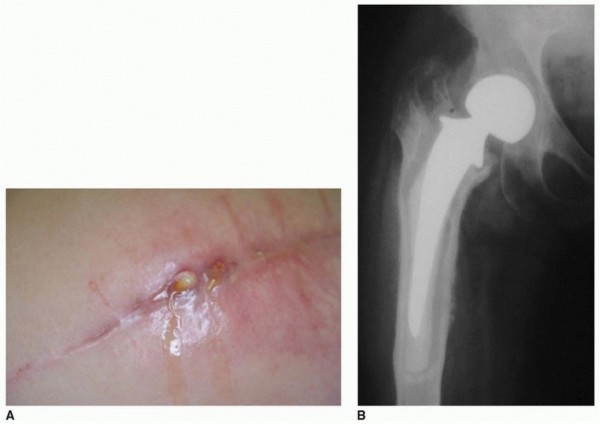

Principles, Planning, and Decision Making Revision total hip arthroplasty is complex and demanding. The stake…

Extended Trochanteric Osteotomy BACKGROUND P. Maxwell Courtney Wayne G. Paprosky Removal of well-fixed femora…